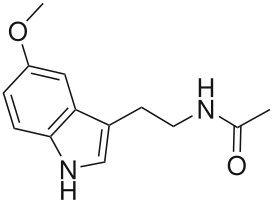

Синтез

Пинеалоциты синтезируют мелатонин, сначала преобразуя аминокислоту триптофан в серотонин. Затем серотонин ацетилируется ферментом AANAT и превращается в N-ацетилсеротонин . N-ацетилсеротонин превращается в мелатонин ферментом гидроксииндол O-метилтрансферазой (HIOMT), также известным как ацетилсеротонин O-метилтрансфераза (ASMT). Активность этих ферментов высока ночью и регулируется ранее обсуждавшимися механизмами, включающими норадреналин[1].